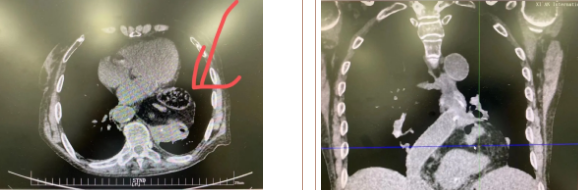

據(jù)了解,患者多年來進(jìn)食后出現(xiàn)惡心、嘔吐,卻未到醫(yī)院進(jìn)行檢查。3個(gè)月前患者突然出現(xiàn)無尿,全身腫脹等情況才前往就醫(yī),卻遭多家醫(yī)院拒收,輾轉(zhuǎn)來到我院就診。檢查發(fā)現(xiàn)患者已患宮頸癌、進(jìn)而引起腎后性腎衰、同時(shí)合并膈疝、出現(xiàn)泌尿道感染,病情及其復(fù)雜。

經(jīng)泌尿外科積極救治,患者腎衰癥狀緩解,隨后轉(zhuǎn)入放射治療中心進(jìn)行宮頸癌根治性放療。放療期間,患者惡心、嘔吐癥狀逐漸加重,后期無法進(jìn)食,排除機(jī)械性腸梗阻和放療因素,考慮因長期膈疝加重引起,經(jīng)胸外科會(huì)診后轉(zhuǎn)入胸外科一病區(qū)準(zhǔn)備手術(shù)治療。

麻醉手術(shù)中心副主任丁倩為減輕患者術(shù)后不適,實(shí)施單腔聯(lián)合支氣管封堵插管,同時(shí)進(jìn)行了肋間神經(jīng)阻滯麻醉。術(shù)中發(fā)現(xiàn)患者膈疝巨大,食管和疝囊分界不清,部分胃組織和結(jié)腸疝已進(jìn)入胸腔。李文海憑借豐富的臨床經(jīng)驗(yàn),仔細(xì)辨別解剖變異,有序完成分離、縫合、修補(bǔ)等一系列操作,胸外科穆強(qiáng)副主任醫(yī)師、劉歡住院醫(yī)師、麻醉手術(shù)中心團(tuán)隊(duì)通力配合,手術(shù)最終順利完成,患者安全返回胸外科監(jiān)護(hù)室病房。目前患者術(shù)后恢復(fù)良好,于近日準(zhǔn)備出院。